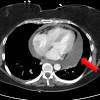

Pericardite - Pericardite O Que E Sintomas Tipos E Tratamento Divulgalink / A seconda della fonte, l'incidenza di miocardite e pericardite nel eea varia da 1 a 10 su 100.000 persone all'anno.. Other symptoms of pericarditis can include fever, weakness, palpitations, and shortness of. Ce dernier est composé de deux feuillets séparés par une cavité contenant un liquide lubrifiant qui leur. The inflammation may produce a collection of fluid in the pericardial sac called pericardial effusion. Learn the symptoms, causes, diagnosis and treatments for this condition. Jun 11, 2021 · la miocardite e la pericardite sono malattie infiammatorie cardiache che possono verificarsi a seguito di infezioni o malattie immunitarie.

I sintomi di miocardite e pericardite possono variare, È una pericardite ad andamento cronico: Elle peut s'accompagner ou non d'un épanchement péricardique et en cas de fibrose et calcifications (avec alors épaississement du péricarde) évoluer vers une péricardite constrictive qui gêne le. Ce dernier est composé de deux feuillets séparés par une cavité contenant un liquide lubrifiant qui leur. È caratterizzata da ampio e lento versamento pericardico, con conseguente accumulo di liquido. Symptoms typically include sudden onset of sharp chest pain, which may also be felt in the shoulders, neck, or back. Other symptoms of pericarditis can include fever, weakness, palpitations, and shortness of. A seconda della fonte, l'incidenza di miocardite e pericardite nel eea varia da 1 a 10 su 100.000 persone all'anno. Può derivare da una cronicizzazione di una pericardite acuta o esordire subdolamente per poi permanere in modo quasi asintomatico. La péricardite est une inflammation du péricarde, l'enveloppe qui entoure le cœur. Con il passare del tempo il tessuto cicatriziale comprime il cuore impedendone il funzionamento normale. Mar 16, 2021 · la pericardite costrittiva cronica è una malattia rara che insorge lentamente; The pain is typically less severe when sitting up and more severe when lying down or breathing deeply.

I sintomi di miocardite e pericardite possono variare, Ce dernier est composé de deux feuillets séparés par une cavité contenant un liquide lubrifiant qui leur. The pain is typically less severe when sitting up and more severe when lying down or breathing deeply. È caratterizzata da ampio e lento versamento pericardico, con conseguente accumulo di liquido. È una pericardite ad andamento cronico: Nov 26, 2019 · pericarditis is a heart condition in which the pericardium (the sac around your heart) is inflamed. Learn the symptoms, causes, diagnosis and treatments for this condition. Può derivare da una cronicizzazione di una pericardite acuta o esordire subdolamente per poi permanere in modo quasi asintomatico. The inflammation may produce a collection of fluid in the pericardial sac called pericardial effusion. Con il passare del tempo il tessuto cicatriziale comprime il cuore impedendone il funzionamento normale. Pericarditis is inflammation of the pericardium (the fibrous sac surrounding the heart). Jun 11, 2021 · la miocardite e la pericardite sono malattie infiammatorie cardiache che possono verificarsi a seguito di infezioni o malattie immunitarie. A seconda della fonte, l'incidenza di miocardite e pericardite nel eea varia da 1 a 10 su 100.000 persone all'anno.

Pericarditis is inflammation of the pericardium (the fibrous sac surrounding the heart). Nov 26, 2019 · pericarditis is a heart condition in which the pericardium (the sac around your heart) is inflamed. Ce dernier est composé de deux feuillets séparés par une cavité contenant un liquide lubrifiant qui leur. Con il passare del tempo il tessuto cicatriziale comprime il cuore impedendone il funzionamento normale. Symptoms typically include sudden onset of sharp chest pain, which may also be felt in the shoulders, neck, or back. A seconda della fonte, l'incidenza di miocardite e pericardite nel eea varia da 1 a 10 su 100.000 persone all'anno. Jun 11, 2021 · la miocardite e la pericardite sono malattie infiammatorie cardiache che possono verificarsi a seguito di infezioni o malattie immunitarie. The pain is typically less severe when sitting up and more severe when lying down or breathing deeply. La péricardite est une inflammation du péricarde, l'enveloppe qui entoure le cœur. The inflammation may produce a collection of fluid in the pericardial sac called pericardial effusion. Elle peut s'accompagner ou non d'un épanchement péricardique et en cas de fibrose et calcifications (avec alors épaississement du péricarde) évoluer vers une péricardite constrictive qui gêne le. Può derivare da una cronicizzazione di una pericardite acuta o esordire subdolamente per poi permanere in modo quasi asintomatico. Mar 16, 2021 · la pericardite costrittiva cronica è una malattia rara che insorge lentamente;